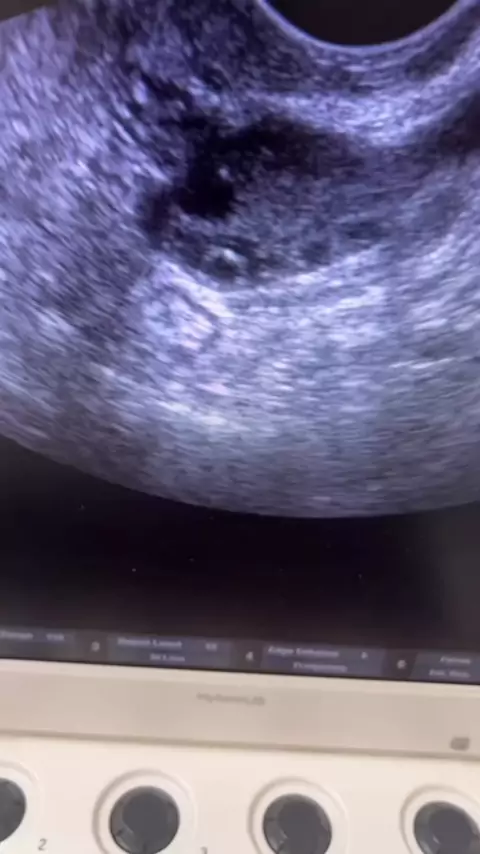

✨ Sim, é possível engravidar mesmo com Síndrome dos Ovários Policísticos (SOP)! ✨ Muitas mulheres acreditam que ter SOP significa não poder ter filhos, mas isso não é verdade. ✅ Com diagnóstico preciso, acompanhamento médico e um plano de tratamento individualizado, é possível regular os hormônios, melhorar a ovulação e aumentar as chances de gravidez natural. Na Clínica Casil, oferecemos: 🔹 Consulta online para avaliar seus exames. 🔹 Plano de acompanhamento personalizado